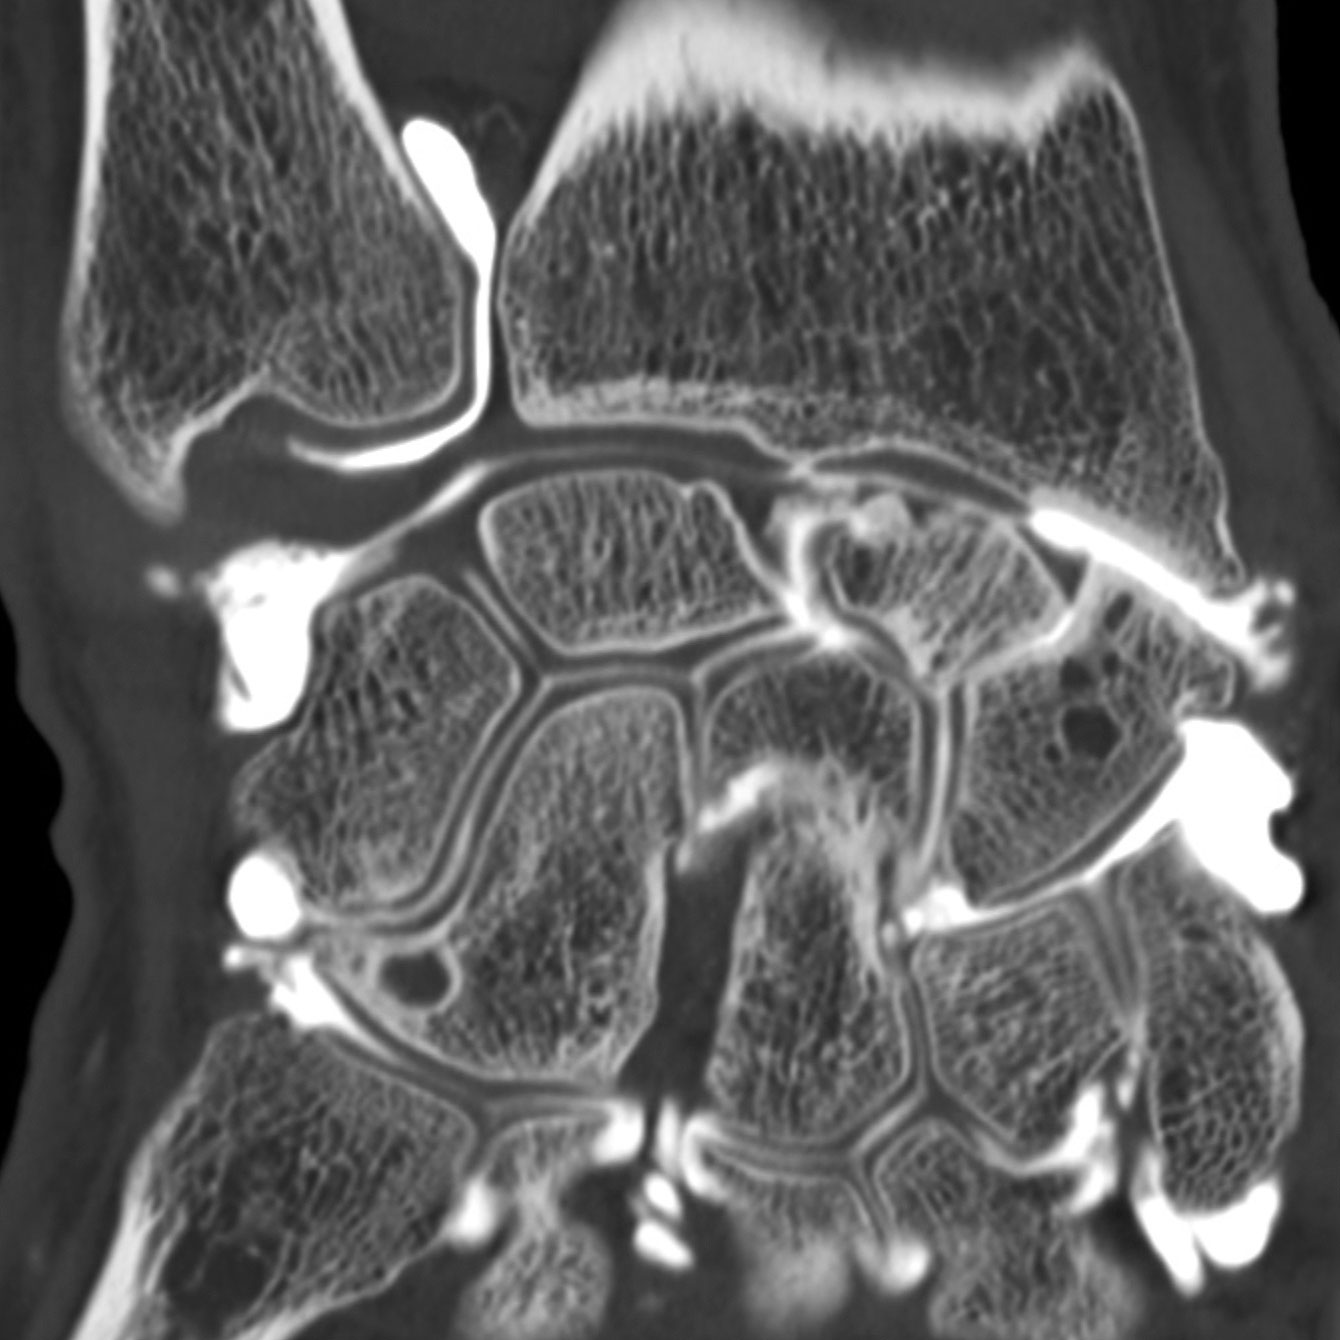

Arthroscanner images d'examen